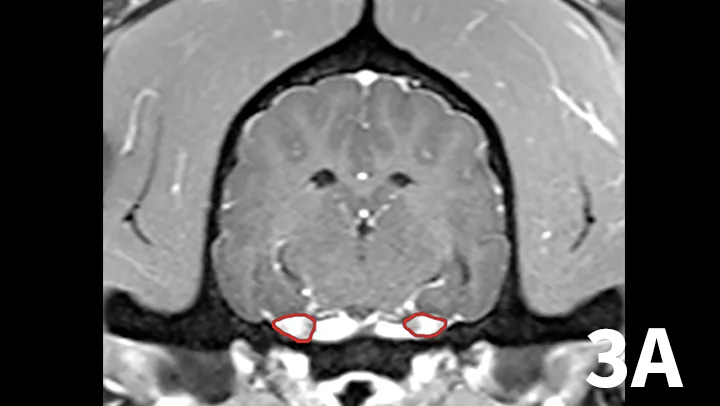

Animals may have erythema and pruritus affecting the external ear or pinna, odor or discharge from the ear, and pain in addition to signs of peripheral vestibular disease. Although diagnosis can be suggested by otoscopy, advanced imaging is superior, as it permits visualization of the osseous bulla and inner ear. The author typically prefers MRI to image dogs suspected of otitis interna because it is superior to computed tomography (CT) for detecting intracranial extension of lesions and detecting other causes masquerading as otitis interna. On MRI, bullae may appear thickened and are usually filled with T2-hyperintense/T1–iso-hypointense (dark) material; abnormal tissue within the bulla usually contrast-enhances T1WI (Figure 2). On T2WI, there may be a loss of signal within the inner ear. Myringotomy and deep ear flush are recommended to identify the underlying infectious agent and assist in removing debris or pus that will prohibit clearance of infection. Antimicrobial therapy is typically continued for 6 to 8 weeks, as bone infection is likely.

Transverse T2WI (A) and T1WI (B) from a 6-year-old cocker spaniel with a 6-month history of left peripheral vestibular disease that acutely worsened, with signs consistent with central localization. The left middle ear cavity is filled with T2-hyperintense material (arrowhead). The left inner ear is hypointense (arrow) compared with the right side. In addition, the left medulla and cerebellum contains patchy T2-hyperintense lesions. T1 postcontrast images show enhancement of the meninges (arrowhead) and a mass-like, enhancing lesion adjacent to the internal acoustic meatus. These findings are consistent with chronic otitis interna and media with secondary extension into the meninges and central nervous system.